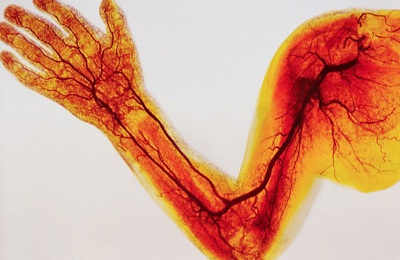

Ehhez a test egy nagyon jól kidolgozott artériás és vénás hálózat, amely behatol minden szöveteket és szerveket. Ha problémák vannak ezzel a mechanizmussal, vannak bizonyos tünetek emberben.

- artériák és arteriolák;

- vénák és venulák;

- kapillárisok és a mikrokeringést.